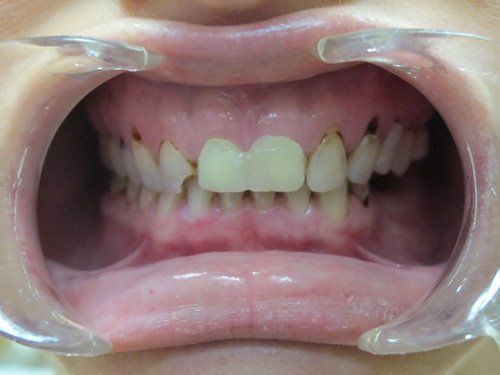

Smile Restoration Procedure

Patient needed multiple restorations, decay removed from upper teeth, crowns placed from canine to canine. Patient Missing 1st lower molar, implant and crown placed, chewing function restored. 2nd molar cracked, causing severe pain, nerve removed from tooth with root canal therapy